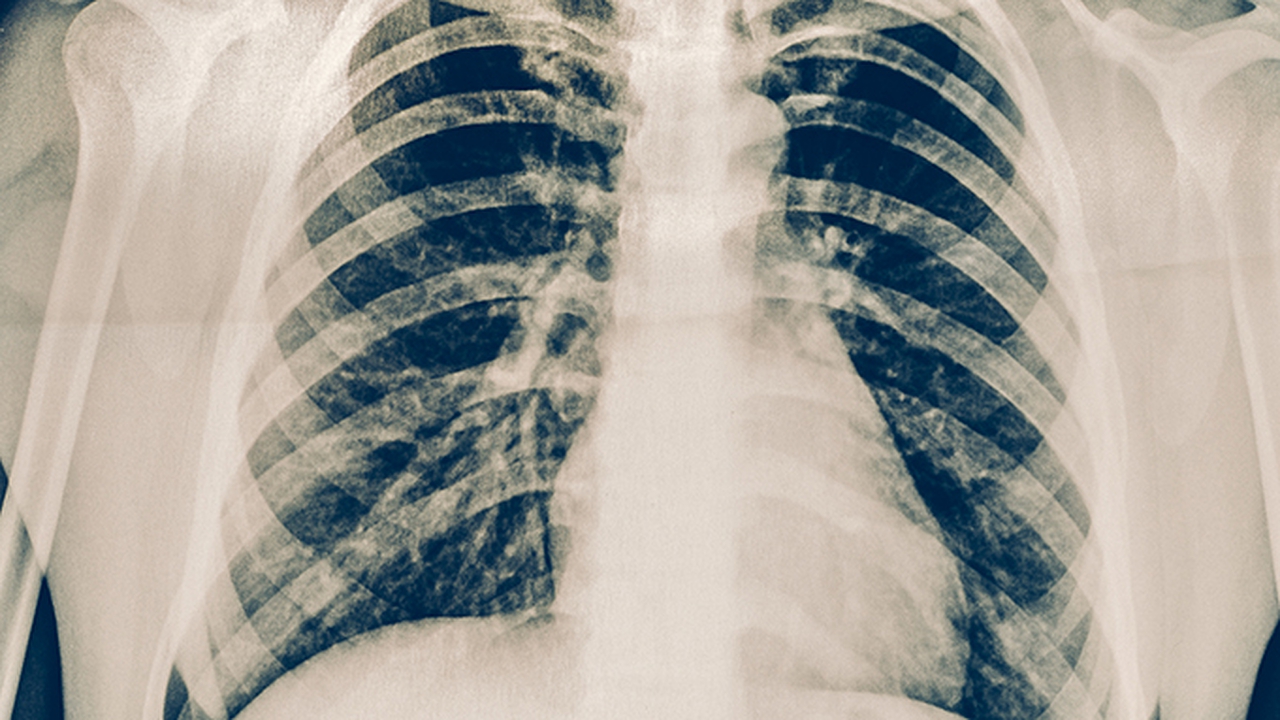

肿瘤预防需建立健康生活方式:保持规律作息,每日摄入500克以上新鲜蔬果,限制加工肉类摄入。40岁以上人群建议每年进行低剂量螺旋CT(肺癌筛查)和胃肠镜检查。注意控制体重(BMI18.5-23.9)、戒烟限酒,长期接触致癌物职业人群需做好防护。出现不明原因消瘦、持续疼痛或异常出血时应及时就医筛查。